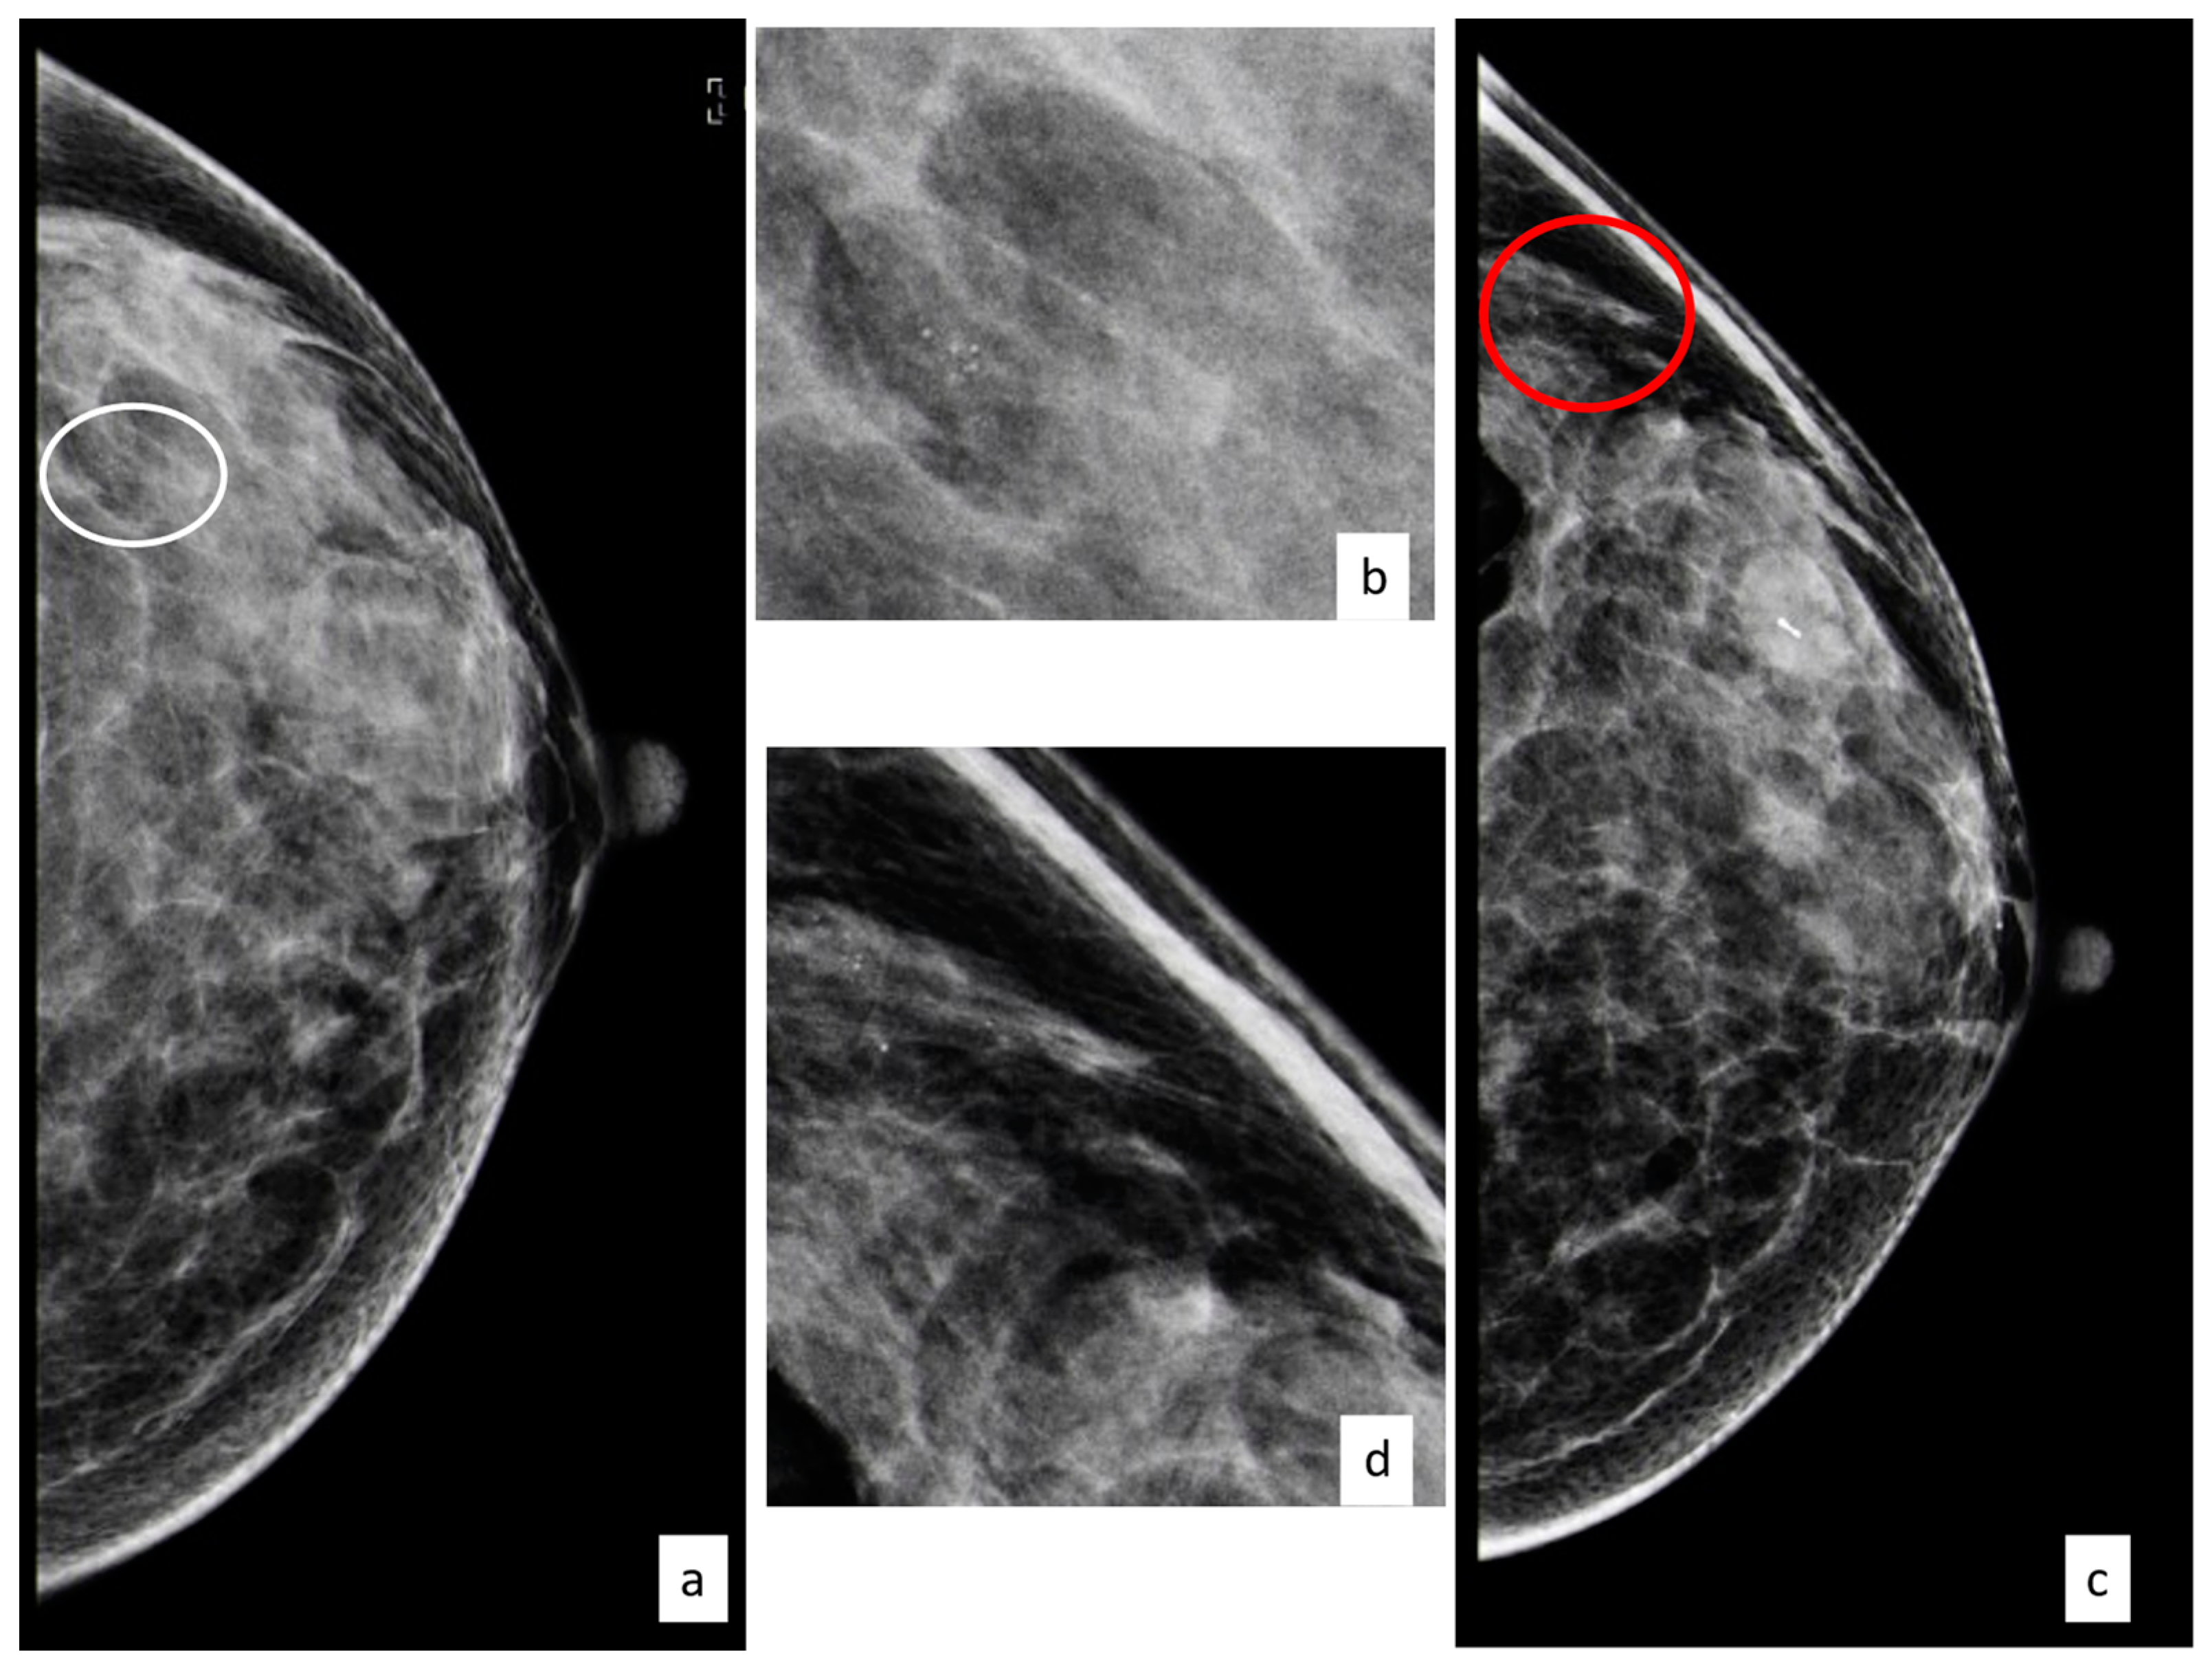

3.3.1. Flat Epithelial Atypia

3.3.2. Atypical Ductal Hyperplasia

3.3.3. Lobular Intraepithelial Neoplasia

3.3.4. Atypical Papillary Lesion

3.3.5. Phyllodes Tumors

3.3.6. Radial Scar